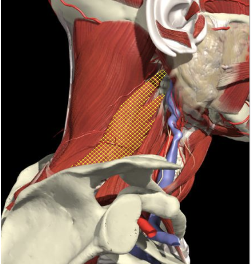

Laterocollis

Cervical Dystonia

Muscle Selection

Long muscles transversing spine

Levator scapulae

Scalenus Anterior/medius

Semispinalis cervicis

Longissimus cervicis

Biomechanical advantage

Range - 37 degrees